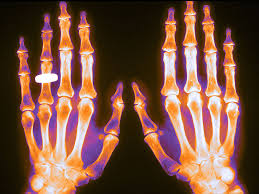

JAMA, 17 de enero de 2017 Las fracturas debidas a la osteoporosis representan un serio y costoso problema de salud pública, que conduce a la discapacidad y a un mayor riesgo de mortalidad. Para las mujeres posmenopáusicas, las fracturas osteoporóticas son más comunes que el ictus, el infarto de miocardio y el cáncer de mama combinados.

El cambio en la densidad mineral ósea con el tratamiento se relaciona con la ocurrencia de fracturas

Aunque el intervalo ideal entre densitometrías no está establecido, la estabilidad o aumento de la DMO entre estudios se asocia a un mejor pronóstico. Annals of Internal Medicine, 19 de julio de 2016